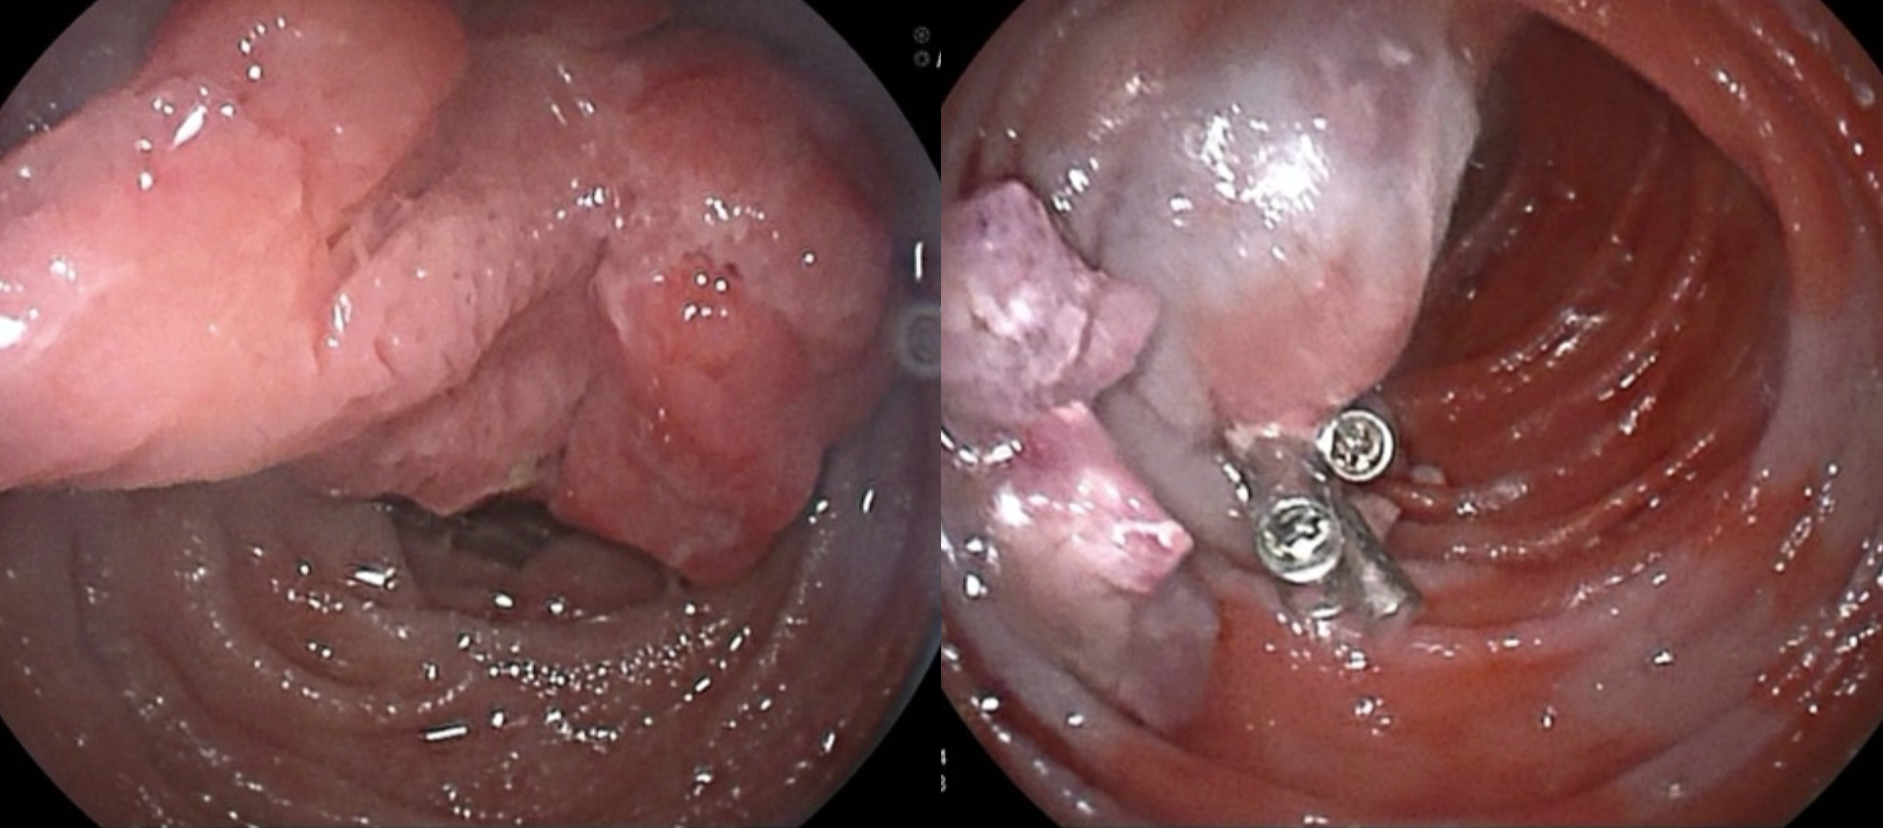

巨大息肉(近10cm)在小肠镜下分块切除。内镜术后平稳后出院